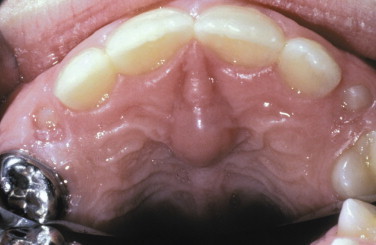

What is the raised area on anterior palate?

(it also involves bone)

Nasopalatine duct cyst